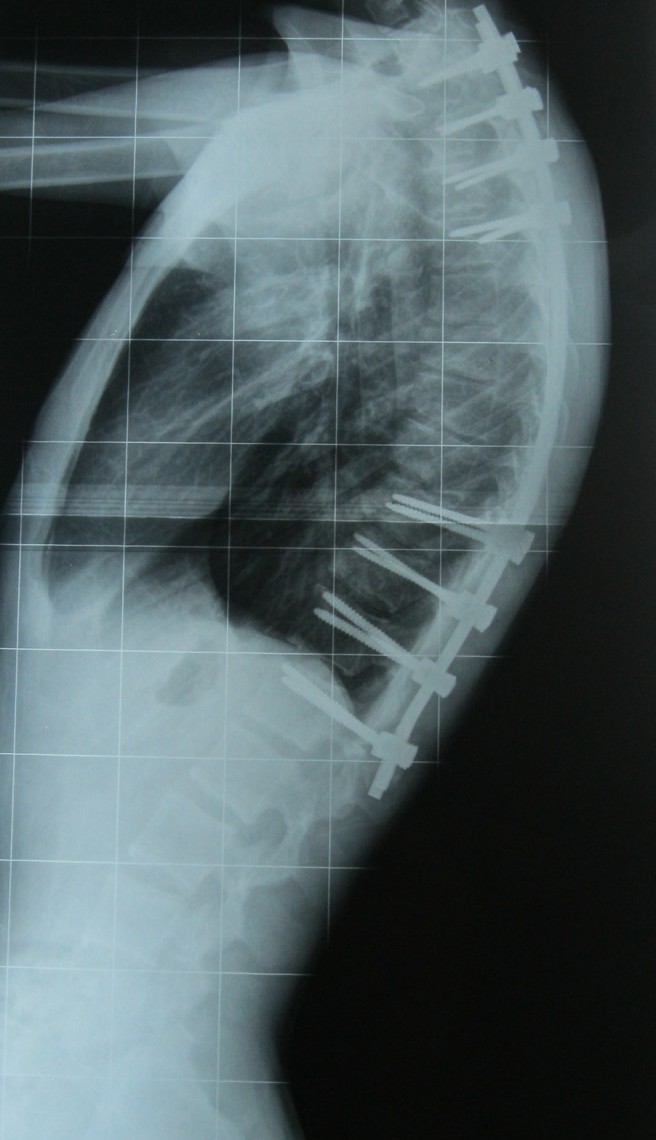

Scheuermann kifozu olan bir hastanın ameliyat öncesi ve sonrası fotoğrafı görülüyor.